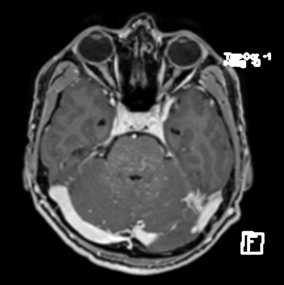

extremidades, marcha atáxica. La RNM de cerebro simple y contrastada evidencia múltiples

lesiones hipointensas en T1, hiperintensas en T2 y FLAIR con realce heterogéneo (patrón

en sal y pimienta) localizadas en puente y hemisferios cerebelosos. LCR documenta

Figura 1

El gold standard es la resonancia magnética de cerebro que puede evidenciar en puente

muestran imágenes puntiformes con aspectos de "sal y pimienta" o curvas con absorción de contraste. (6) Este tipo de lesiones son de mayor predominio puente, pero se pueden

evidenciar en otras regiones SNC, como cerebelo. (5). Este tipo de lesiones no suelen ser

mayor a 3 mm de diámetro, con un patron de distribución el cual disminuye en número al

alejarse de la protuberancia, pero pueden extenderse al cerebro y médula espinal.(3)